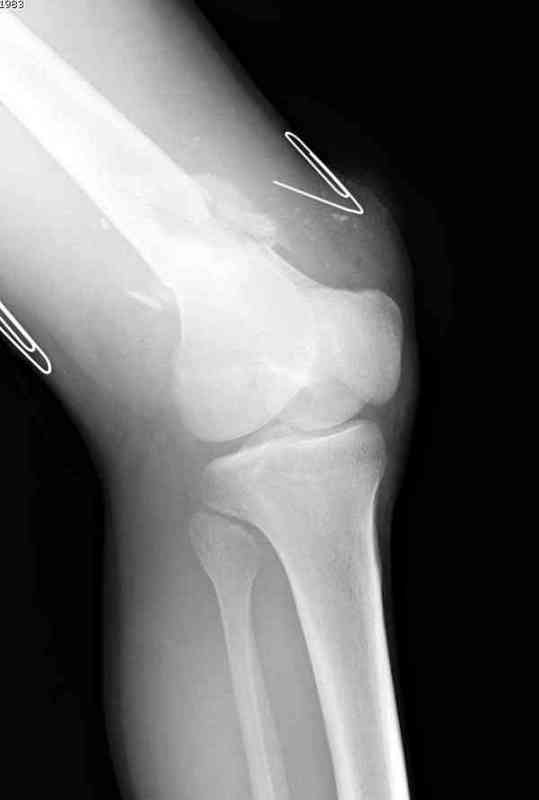

Пострадавшему 23, пистолетная огнестрельная не кроветочащая рана, меньше одного см диаметром, входное отверстие расположено латерально, и выход передне-медиально, и еще имеется второе пулевое ранение правой navicular bone с этой стороны.

Несмотря на сниженный до 0.9 BI-ankle-brachial-index (обязательное, недорогое исследование при подозрении на повреждение сосудов, рассчитанный по разнице давления в нижней и верхней конечности), последующее КТ ангиограмма не подтвердила повреждения артериальных сосудов.